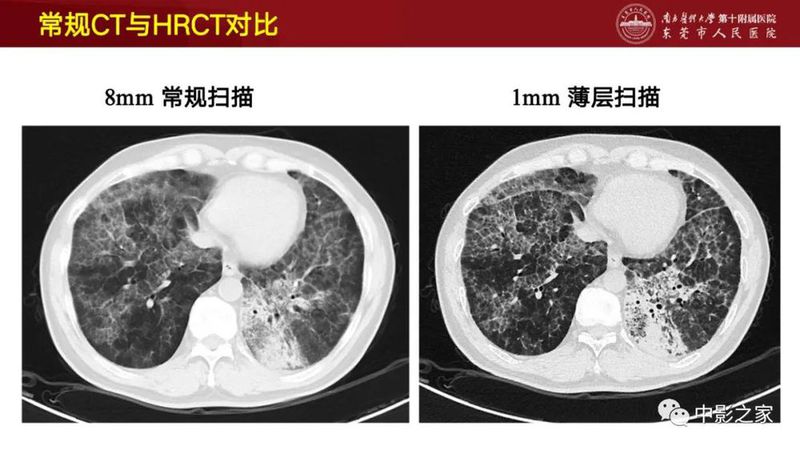

结缔组织相关间质性肺疾病(CTD-ILD)很难,这篇说清楚了!